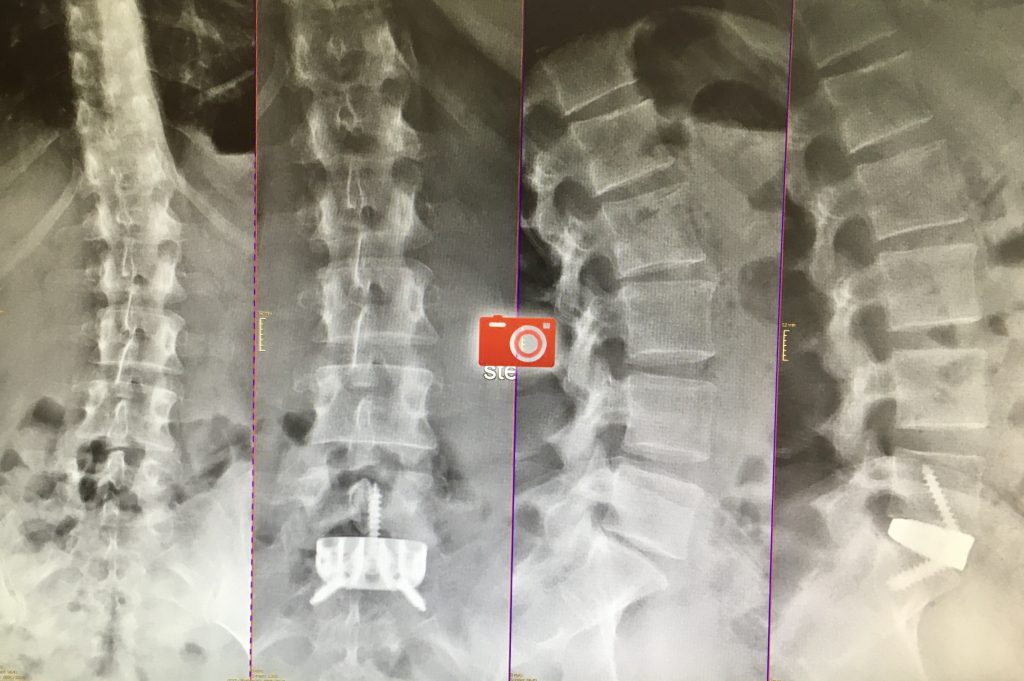

Existen múltiples técnicas para conseguir la fusión de la columna lumbar. La artrodesis posterior instrumentada es la técnica más habitual. Consiste en colocar tornillos de fijación en las vértebras, y un implante a nivel del disco (caja intervertebral), lo que permite liberar nervios en el canal espinal y reconstruir la columna de un modo muy efectivo. La técnica habitual se denomina TLIF (transforaminal lumbar interbody fusion). Esta técnica también puede realizarse de forma mínimamente invasiva.

En determinados pacientes el abordaje para colocar la caja puede ser por vía anterior; la técnica se denomina ALIF (anterior lumbar interbody fusion).

Esta técnica permite en pacientes seleccionados respectar la musculatura lumbar y acortando los tiempos de recuperación.Finalmente, esta fusión se puede realizar de manera mínimamente invasiva, con una pequeña incisión a través del lateral del abdomen, lo que se denomina técnica XLIF u OLIF (extrem lateral lumbar interbody fusion).Técnica mínimamente invasiva, utilizada para favorecer la reconstrucción vertebral y fusión en deformidad y casos con afectación de múltiples discos.